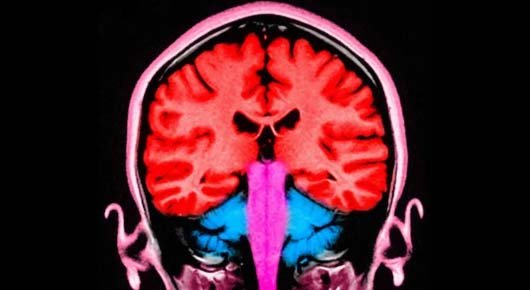

During the experiment, an electrical current was applied to the frontal and parietal areas of the brain – situated at the front and towards the back. When these areas were stimulated at the same time, the participants gave away more money.

Those two brain areas are known to play a role in decision-making and in empathy, or distinguishing the feelings of others from our own.

When a more selfless decision was made, the empathy region and the decision region appeared to communicate.